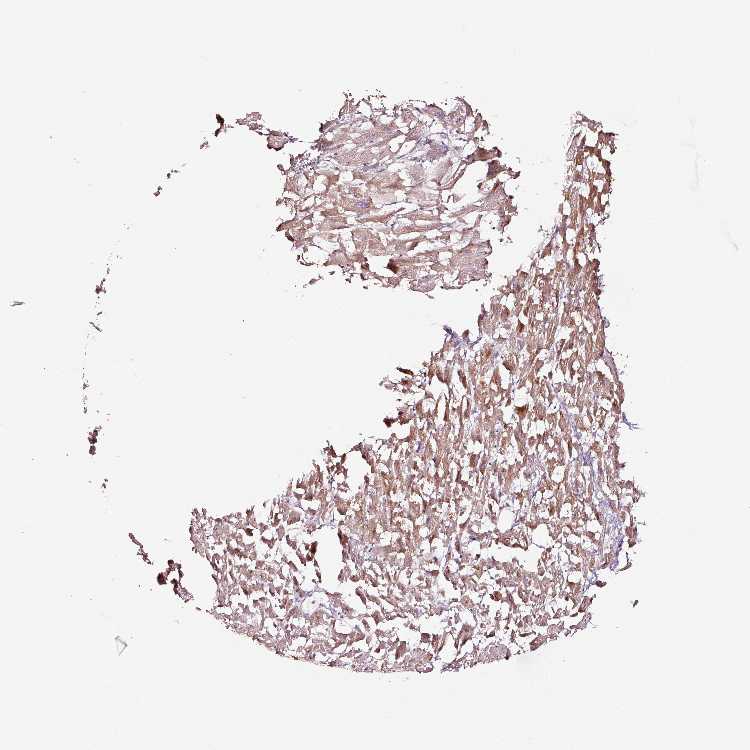

HEART MUSCLE - Antibody stainingi

Antibody staining in the annotated cell types in the current human tissue is reported as not detected, low, medium, or high, based on conventional immunohistochemistry profiling in selected tissues. This score is based on the combination of the staining intensity and fraction of stained cells.

Each image is clickable and will lead to virtual microscopy that enables deeper exploration of all samples and also displays staining intensity scores, fraction scores and subcellular localization as well as patient and tissue information for each sample.

Antibody HPA047089Antibody HPA053624

Cardiomyocytes HighHigh